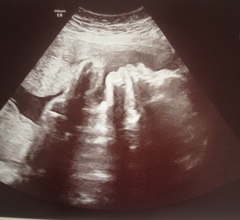

First consultant appt today, she was def having a good look at babes heart, you could see her getting her learning on, she was quite fascinated. Anyway I got a cheeky free 4d scan so, as we've not had many scan pics in a while, here's mine from today @ 28+5

August 2016 number 5 - waddling towards the third trimester!